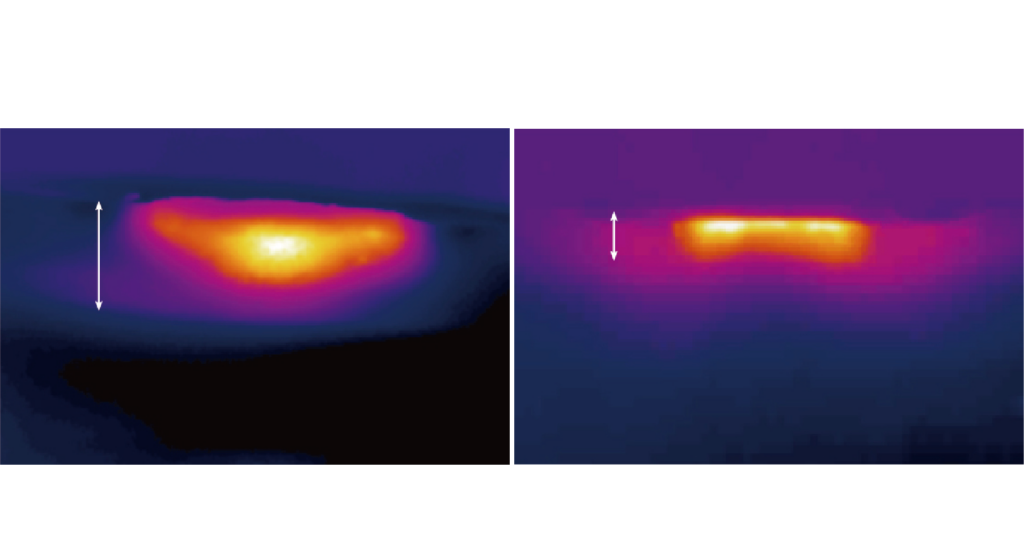

ONDA PRO超微波 熱度影像呈現

右圖

傳統的漸進式加熱為能量從表皮往下擴散,熱能主要先於真皮層吸收,由於表皮熱能過高容易會產生熱燙感而無法使用高能量,因此無法傳遞到深層。

左圖

ONDA超微波採「穿透式加熱」原理,治療時熱能累積在深層下方,大約位在脂肪層產生較高的溫度作用,熱能也能往上擴散至真皮層的網狀區。